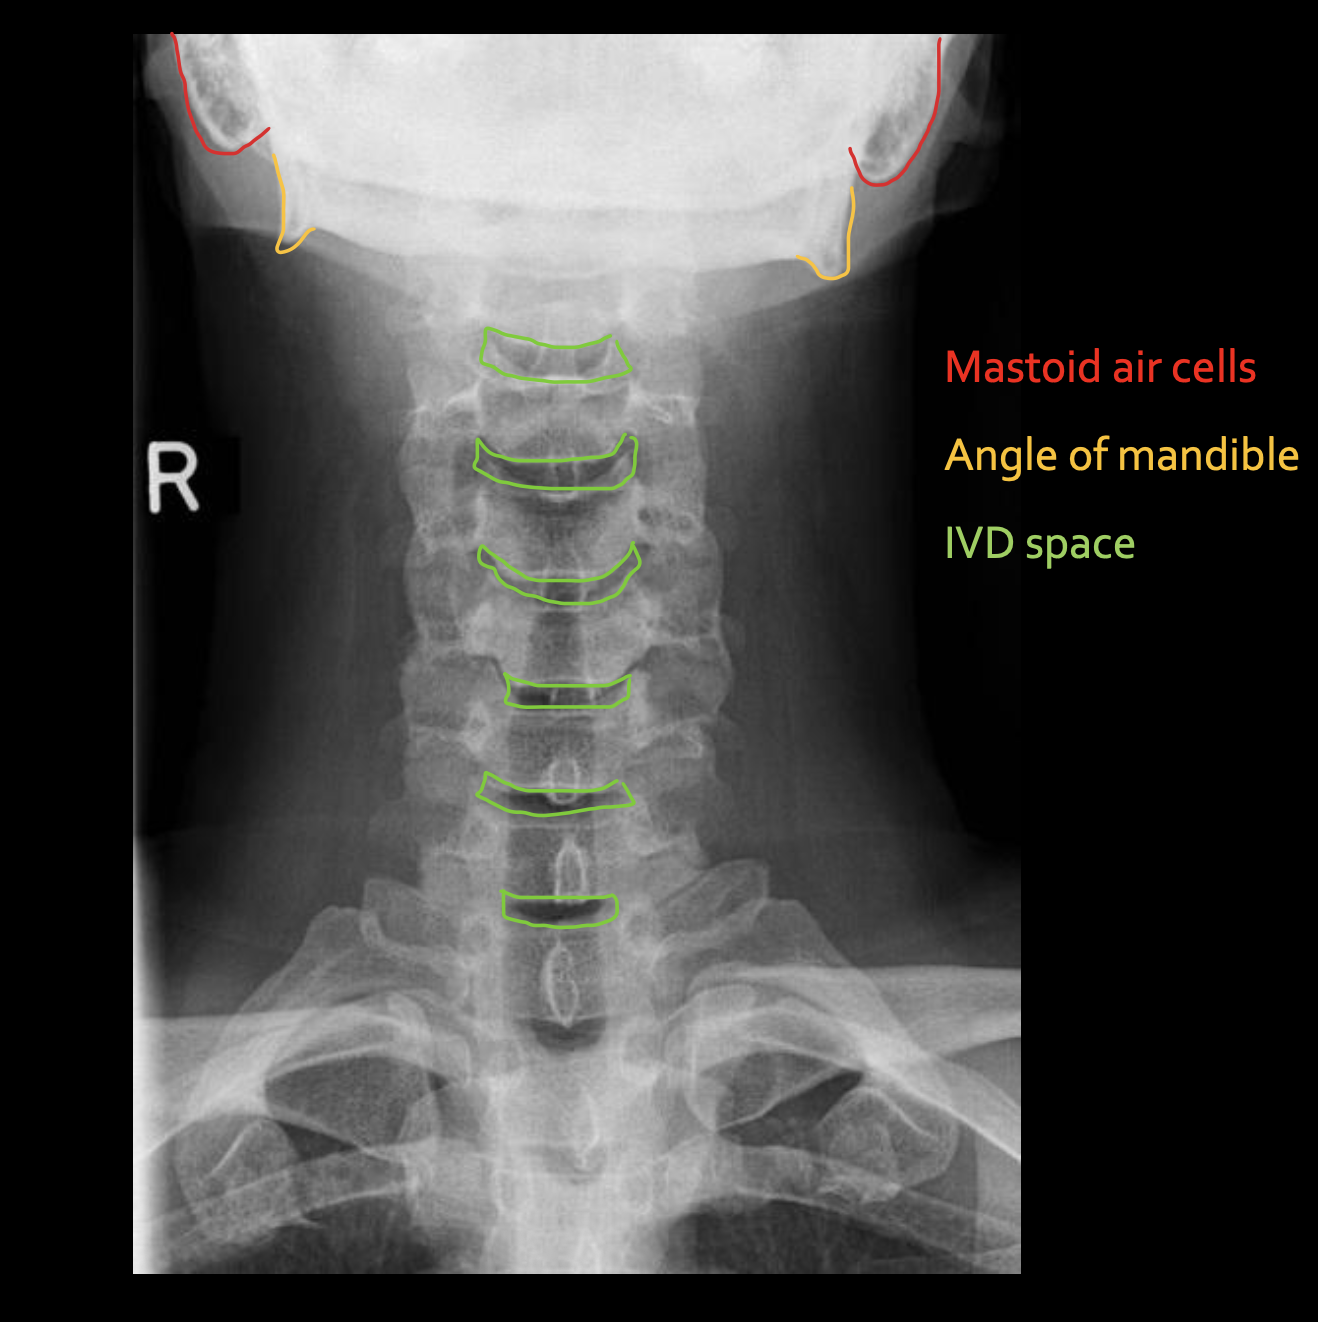

乳突气房

Mastoid air cells

下颌角

Angle of mandible

椎间隙(Intervertebral Disc space)

IVD space